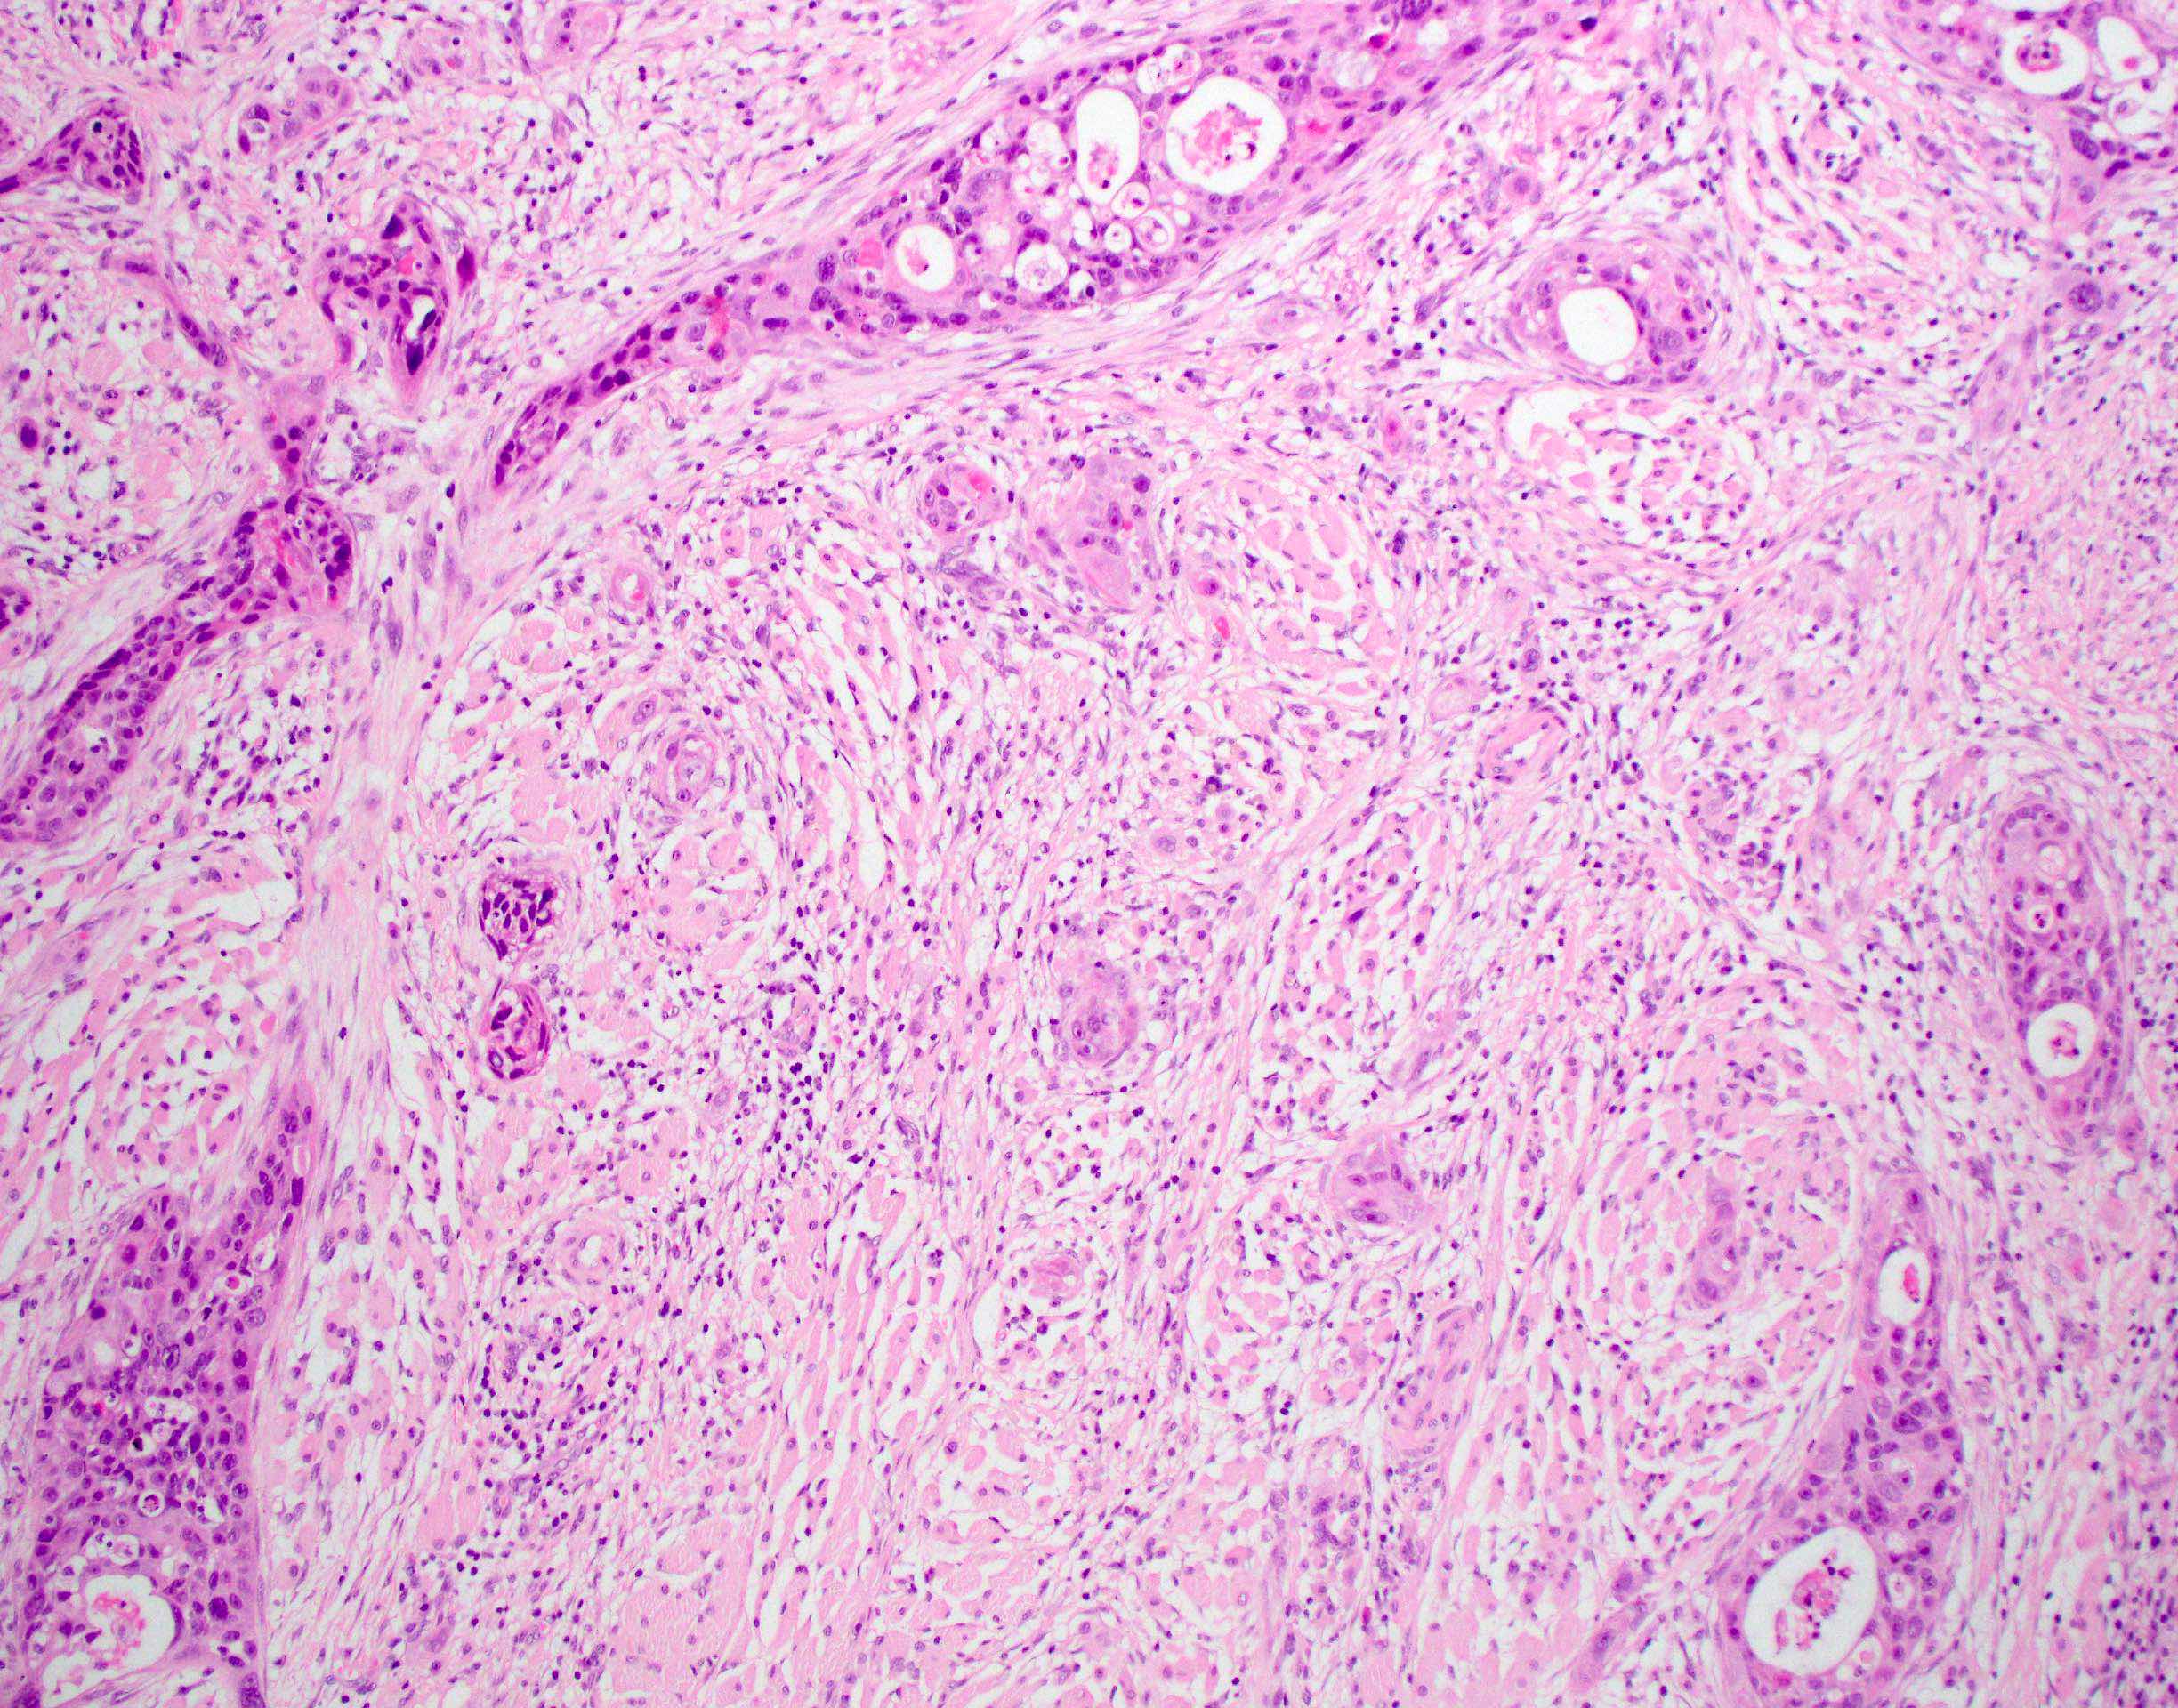

Microscopic (histologic) description

- Squamous cell carcinoma, conventional

- Most common and typical morphology of conventional keratinizing squamous cell carcinoma at any site

- Large polygonal malignant cells with intercellular bridges

- Cytoplasmic or extracellular eosinophilic keratin

- Dyskeratotic cells and squamous pearls

- Nuclear size, pleomorphism, hyperchromasia and mitoses increase with increasing grade

Microscopic (histologic) images

Contributed by Ruta Gupta, M.B.B.S., M.D.